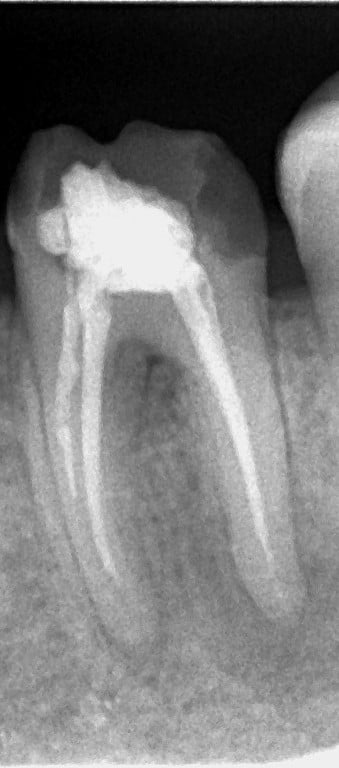

Rentgenový snímek zubu před a po ošetření, kde je vidět, jak pečlivé vyčištění a vyplnění kořenových kanálků obnovuje zdraví zubu a zabraňuje dalším komplikacím.